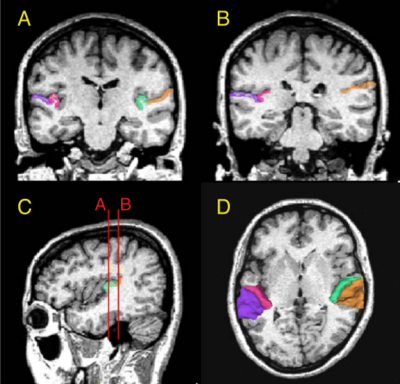

Atlas Guided Identification of Brain Structures by Combining 3D Segmentation and SVM Classification

Publication: MICCAI 2006, LNCS 4191, pp. 209–216, 2006. PDF

Authors: Ayelet Akselrod-Ballin, Meirav Galun, Moshe John Gomori, Ronen Basri, and Achi Brandt

Institution: Department of Computer Science and Applied Math, Weizmann Institute of Science, Rehovot, Israel and Dept. of Radiology, Hadassah University Hospital, Jerusalem, Israel

Background/Purpose: This study presents a novel automatic approach for the identification of anatomical brain structures in magnetic resonance images (MRI). The method combines a fast multiscale multi-channel three dimensional (3D) segmentation algorithm providing a rich feature vocab ulary together with a support vector machine (SVM) based classifier. The segmentation produces a full hierarchy of segments, expressed by an irregular pyramid with only linear time complexity. The pyramid provides a rich, adaptive representation of the image, enabling detection of various anatomical structures at different scales. A key aspect of the approach is the thorough set of multiscale measures employed throughout the segmentation process which are also provided at its end for clinical analysis. These features include in particular the prior probability knowl- edge of anatomic structures due to the use of an MRI probabilistic atlas. An SVM classifier is trained based on this set of features to identify the brain structures. We validated the approach using a gold standard real brain MRI data set. Comparison of the results with existing algorithms displays the promise of our approach.